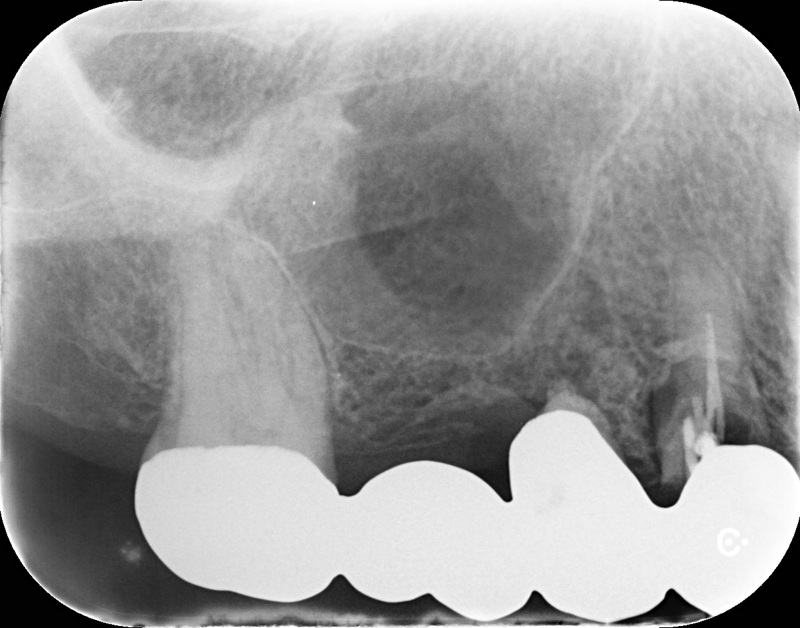

| 治療名 | 抜歯即時インプラントとソケットリフトによる上顎臼歯部の修復症例 |

| 治療説明 |

歯の根が破折していたため抜歯が必要となり、患者さんとご相談のうえ、インプラントによる治療を選択しました。 ただし、インプラントを支える骨の高さが不足していたため、**上顎洞に骨を足す“ソケットリフト”**を併用し、安全にインプラントを埋入しました。 |

| 治療回数・期間 | 約3ヶ月 |

| 副作用とリスク |

・入れ歯や従来のブリッジと比べて、治療期間が長くなる傾向があります。 |

| 料金(税込) | 小規模GBR:110,000円 ソケットリフト:165,000円 インプラント一次手術:220,000円 二次手術:55,000円 上部構造〈セラミック〉:165,000円 合計:715,000円 |